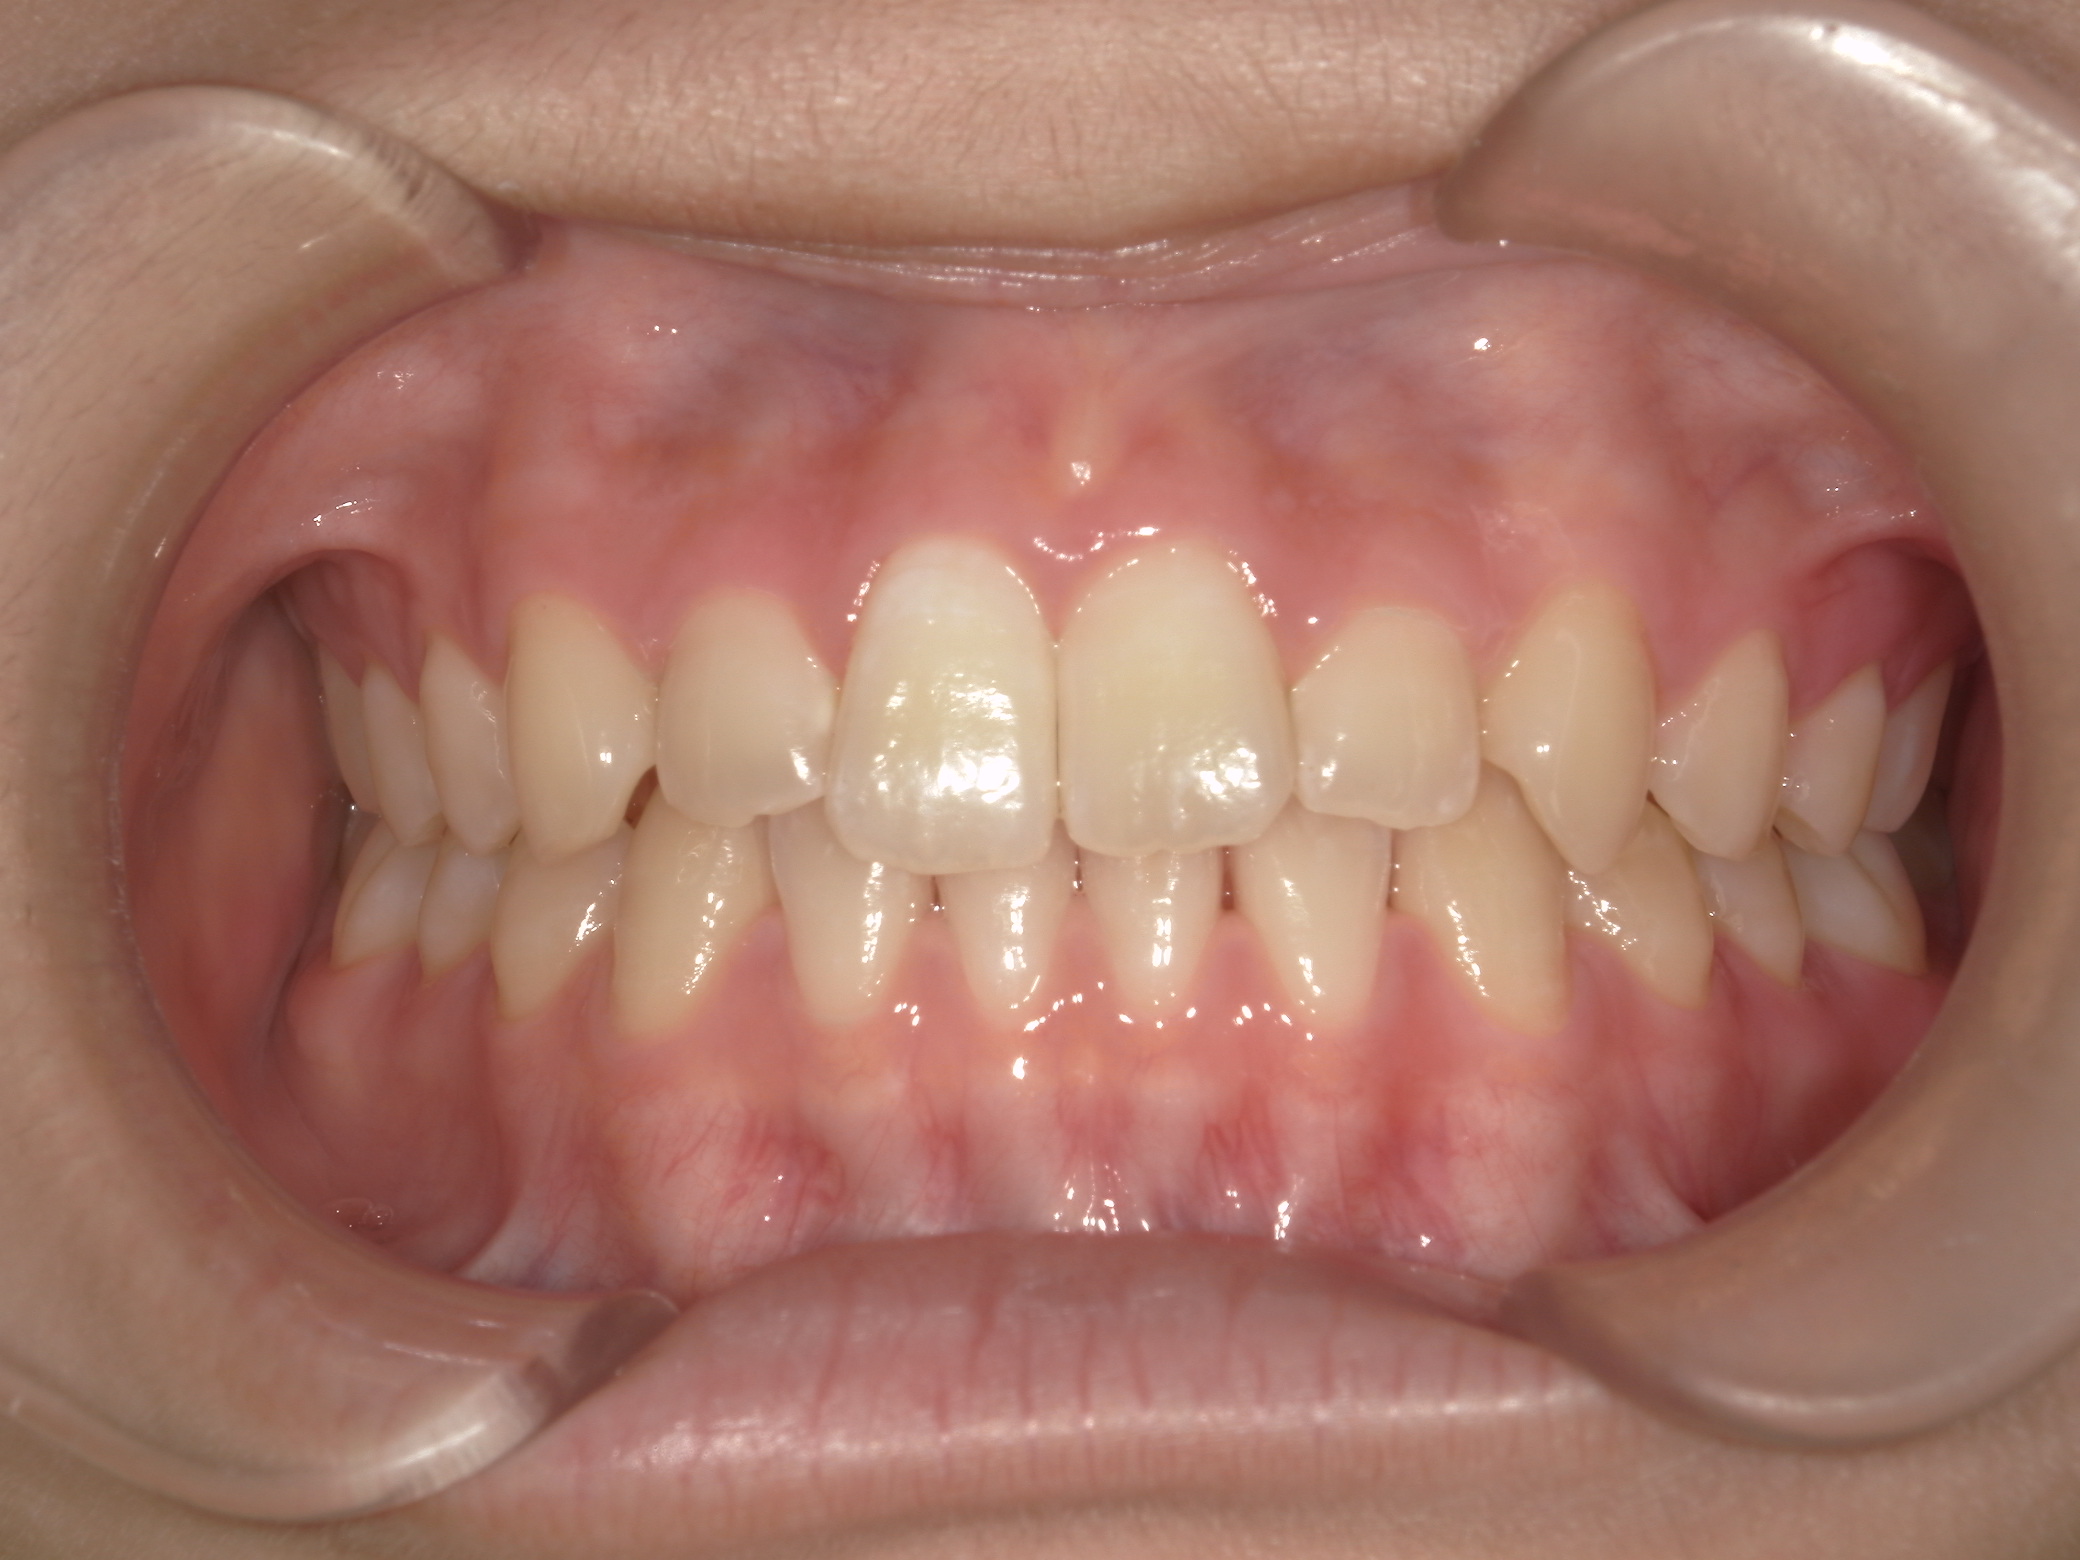

【小学生】マイオブレース矯正 受け口を改善 ①

小学生で開始

マイオブレース

受け口

1期治療のみで改善

Before

After

治療期間

1年11カ月年

治療開始

10歳

種類

マイオブレース矯正

使用装置

機能矯正装置

コメント

毎日装置の装着と MFT 口腔筋機能療法 に取り組んでくれたためスムーズに終わりました。

上顎前歯の並びをもう少し別の装置で改善することも提案しましたが、本人、保護者の方ともに

今の歯並びで満足しているということだったのでこれで終了しています。

MFTを頑張ってくれたため、お口の筋肉バランスもよく、後戻りもしていません。